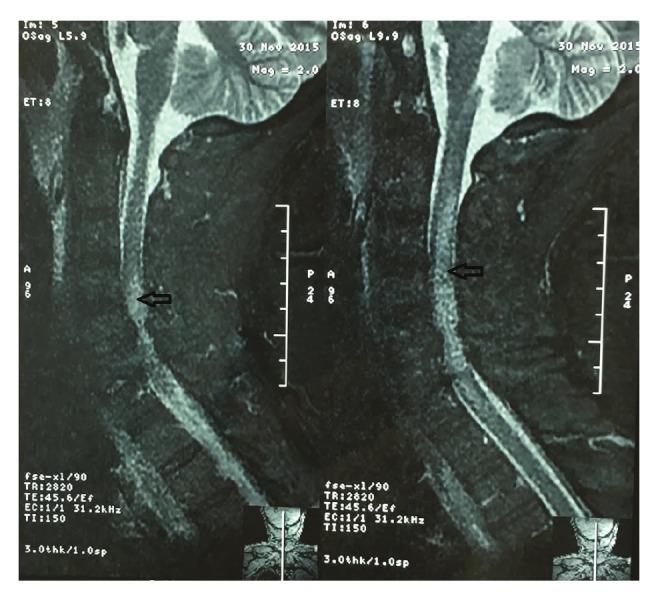

Adult cardiac surgery is associated with significant perioperative morbidity and mortality rates, mainly in elderly patients with co-morbidities. A series of postoperative complications may arise and delay the recovery of patients undergoing cardiac surgery. Such complications also increase the burden of resource use and may affect late survival rates. Neurological complications appear mainly as stroke of varying degrees, with impairment of mobility and ability of the patient. We describe a rare case of progressive paraparesis after on-pump coronary artery bypass grafting, and review its aetiology, diagnosis and management.

成人心脏手术围手术期发病率和死亡率较高,主要见于伴有合并症的老年患者。一系列术后并发症可能出现并延迟心脏手术患者的康复。这些并发症还会增加资源使用负担,并可能影响远期生存率。神经并发症主要表现为不同程度的中风,导致患者活动能力和自理能力受损。我们描述了一例体外循环冠状动脉旁路移植术后进行性双下肢轻瘫的罕见病例,并对其病因、诊断和治疗进行综述。